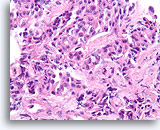

Ductaal carcinoom, Mannenborst FNA, celblok.

Hooggradige nucleaire atypie, necrotisch materiaal, discohesie en vrije stratificatie kunnen worden waargenomen.

Ductaal carcinoom, Mannenborst FNA, celblok.

Hooggradige nucleaire atypie, necrotisch materiaal, discohesie en vrije stratificatie kunnen worden waargenomen.

Ductaal carcinoom, Mannenborst FNA, celblok.

Apoptotische fragmenten, necrotisch materiaal, discohesie, vrije stratificatie en hooggradige nucleaire atypie kunnen duidelijk worden waargenomen.

Ductaal carcinoom, Mannenborst FNA, celblok.

Apoptotische fragmenten, necrotisch materiaal, discohesie, vrije stratificatie en hooggradige nucleaire atypie kunnen duidelijk worden waargenomen.